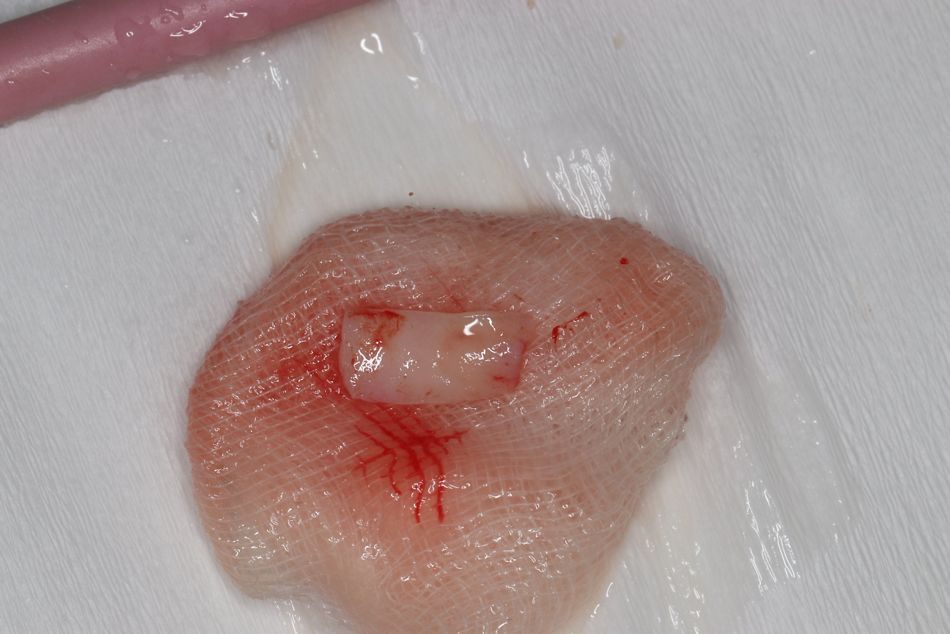

Für ein optimales Weichgewebemanagement und eine adäquate Rot-Weiß-Ästhetik sollte die keratinisierte periimplantäre Mukosa chirurgisch erhalten werden. Hierfür wurden aus dem hinteren Gaumenbereich zwei freie Schleimhauttransplantate (FST) entnommen (Abb. 10) und auf einer Glasplatte mit dem Skalpell entepithelisiert. Die Spenderregion ist mit einem Histoacryl-Kleber primär verschlossen worden. Die entsprechend vorbereiteten Transplantate wurden bukkal und oberhalb der Insertionsstelle hier als Punch mit Einzelknopfnähten (07 Seralene) vernäht und so das gingivale Gewebe maximal gestützt und erhalten werden (Abb. 11).